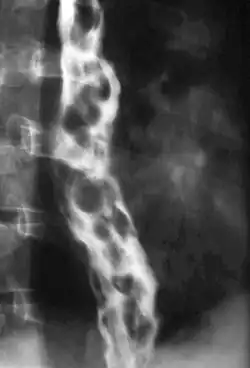

Varice œsophagienne

Les varices œsophagiennes sont dues à une dilatation des veines présentes dans la paroi de l’œsophage, secondaire à une augmentation de la pression dans le système porte (hypertension portale dont la cirrhose représente l'essentiel des causes), d'origine alcoolique ou virale.

Le diagnostic se fait par endoscopie digestive haute, on retrouve un aspect de cordons bleuâtres, saillants, au niveau de la partie inférieure de l’œsophage.